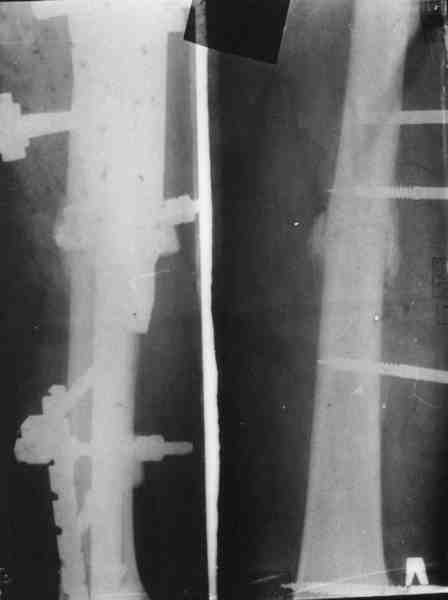

Re: Огнестрельный перелом плеча ( продолжение)

Вот еще информация, ознакамливайтесь pls/